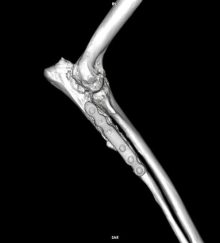

Hock Fracture Repair in Dog with Osteochondritis Dissecans

Repair of hock fracture secondary to osteochondritis dissecans of the medial talar ridge This hock fracture was secondary to ...